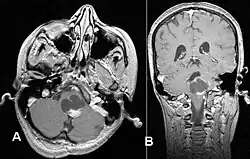

Usually – depending on the interview of the patient and after a clinical exam which includes a neurological exam and an ophthalmological exam – a CT scan and/or an MRI scan will be performed to confirm the presence of a tumor. They are usually easily distinguishable from normal brain structures using these imaging techniques. A special dye may be injected into a vein before these scans to provide contrast and make tumors easier to identify. Pilocytic astrocytomas are typically clearly visible on such scans, but it is often difficult to say based on imaging alone what type of tumor is present.

If a tumor is found, it will be necessary for a neurosurgeon to perform a biopsy of it. This involves the removal of a small amount of tumorous tissue, which is then sent to a (neuro)pathologist for examination and staging.[5] The biopsy may take place before surgical removal of the tumor, or the sample may be taken during surgery to remove the bulk of the tumor.